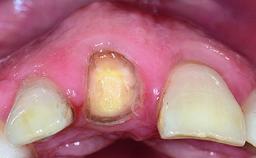

| Abutment Type | CAD/CAM |

| Prosthesis Type | FDP |

| Retention | Cemented, with prosthesis margin < 3mm submucosal Cemented, with prosthesis margin < 3mm submucosal |

| Provisional Implant-Supported Prosthesis | Prosthodontic margin > 3 mm apical to mucosal margin Prosthodontic margin > 3 mm apical to mucosal margin |